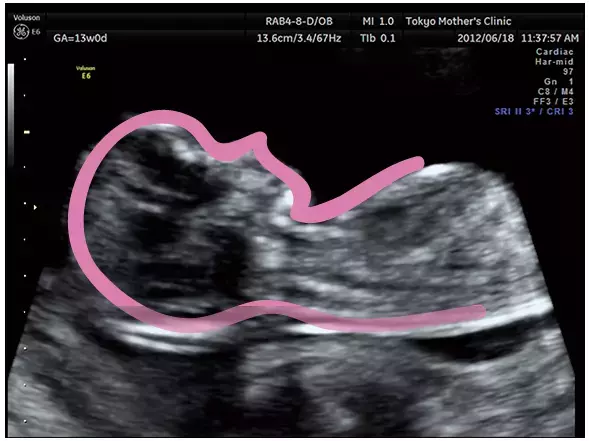

妊娠13週のエコー写真

妊娠4ヶ月のエコー(超音波)写真

横顔の上半身が見えます。うつむいてばかりだった体が、上を向いた姿勢がとれるように。

写真提供:東京マザーズクリニック